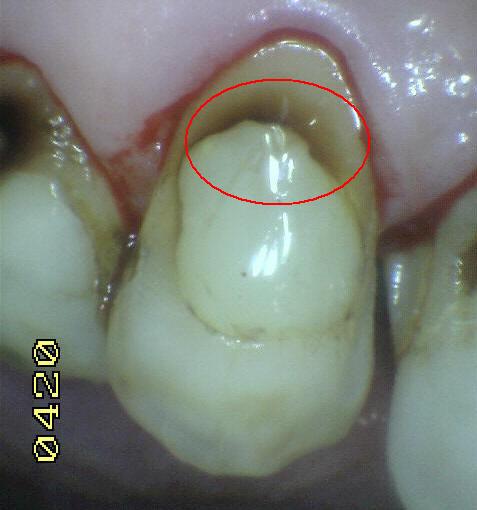

Código 2

(Caries Inicial): Lesión de

caries observada en esmalte en estado húmedo y permanece después de

secar.

- Si el margen de la

restauración está en esmalte, se debe observar el

diente húmedo. Cuando esta húmedo hay una opacidad

compatible con la desmineralización o pigmentación

que no corresponde a la aparencia clínica del

esmalte sano (Nota: la lesión sigue siendo visible

cuando se seca).

- Si el margen de restauración está en dentina: el

Código 2 corresponde a la pigmentación que no es

compatible con la aparencia clínica de la dentina o

el cemento sano.

- (Mancha blanca

/ marrón)